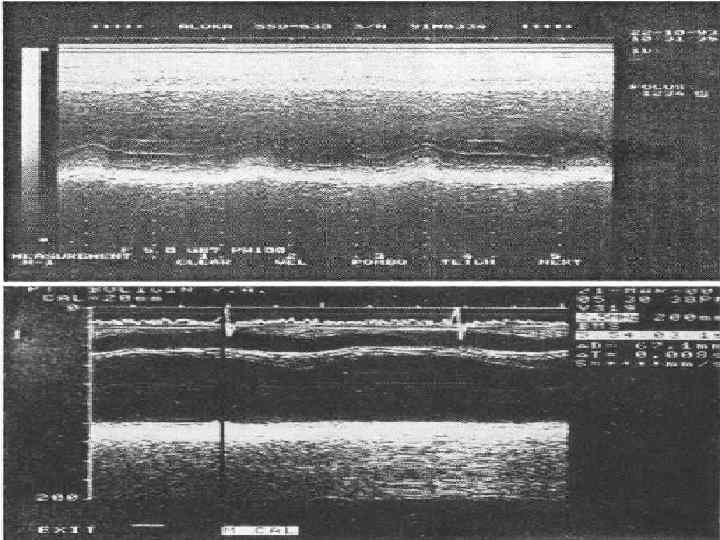

ОЦЕНКА СИСТОЛИЧЕСКОЙ ФУНКЦИИ ЛЕВОГО ЖЕЛУДОЧКА Систолическая функция ЛЖ оценивается по нескольким показателям, центральное место среди которых занимает ударный объем (УО) и фракция выброса (ФВ). Метод Teicholz. До последнего времени расчет УО, ФВ и других гемодинамических показа телей проводился на основании измерений М модальной эхокардиограммы, зарегистрирован ной из левого парастернального доступа. Для расчета учитывается степень передне заднего укорочения ЛЖ, то есть отношения КДР и KCР Расчет проводится по формуле L. Teicholz (где V объем ЛЖ (КСО или КДО) и D переднезадний размер ЛЖ в систолу или диасто лу. УО определяется как разница КДО и КСО, а ФВ — как отношение УО к КДО):

Нормативы стандартных измерений в парастернальной позиции 1. Диаметр правого желудочка в конце диастолы 25 38 мм (обычно менее 28 мм). 2. Диаметр LVOT или аортального фиброзного кольца 16 26 мм. 3. Диаметр аорты на уровне синусов Вальсальвы – 24 39 мм. 4. Аорта в области синотубулярного сужения 21 34 мм. 5. Левое предсердие 25 38 мм (в конце систолы). 6. Диаметр левого желудочка в конце диастолы и в конце систолы 37 53 мм (менее 56 мм), 23 36 мм. 7. Диаметр стенки правого желудочка в конце диастолы менее 5 мм. 8. Диаметр межжелудочковой перегородки в конце диастолы менее 12 мм. 9. Диаметр задней стенки левого желудочка в конце диастолы менее 11 мм.